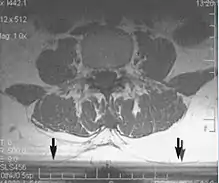

Metal artifacts occur at interfaces of tissues with different magnetic susceptibilities, which cause local magnetic fields to distort the external magnetic field. This distortion changes the precession frequency in the tissue leading to spatial mismapping of information. The degree of distortion depends on the type of metal (stainless steel having a greater distorting effect than titanium alloy), the type of interface (most striking effect at soft tissue-metal interfaces), pulse sequence and imaging parameters. Metal artifacts are caused by external ferromagnetics such as cobalt containing make-up, internal ferromagnetics such as surgical clips, spinal hardware and other orthopaedic devices, and in some cases, metallic objects swallowed by people with pica.[3] Manifestation of these artifacts is variable, including total signal loss, peripheral high signal and image distortion (Figs 3 and 4).[1] Reduction of these artifacts can be attempted by orientating the long axis of an implant or device parallel to the long axis of the external magnetic field, possible with mobile extremity imaging and an open magnet. Further methods used are choosing the appropriate frequency encoding direction, since metal artifacts are most pronounced in this direction, using smaller voxel sizes, fast imaging sequences, increased readout bandwidth and avoiding gradient-echo imaging when metal is present. A technique called MARS (metal artifact reduction sequence) applies an additional gradient, along the slice select gradient at the time the frequency encoding gradient is applied. ==Signal processing dependent artifacts== The ways in which the data are sampled, processed and mapped out on the image matrix manifest these artifacts.[1]